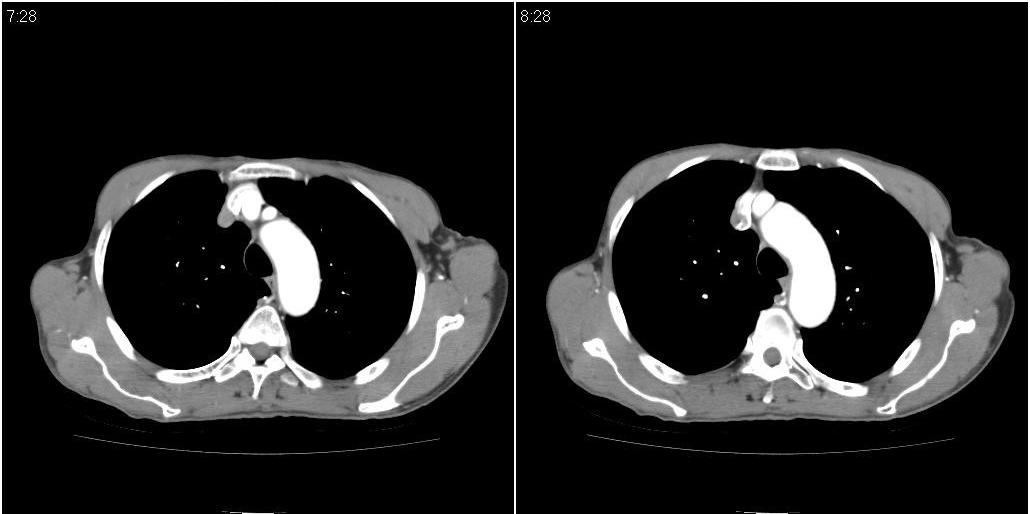

标题: ct增强:

[本贴已被 fanshl 于 2010-3-30 7:14:31 修改过]

右肺中叶阻塞性不张及肺炎,高度怀疑支气管占位,建议纤支镜检查!

考虑右肺中叶感染。左肺下叶支扩。

右中肺阻塞性炎症,建议纤支镜!双下支扩感染。

1)右肺中叶慢性炎症并支气管扩张,节段性肺不张。2)两肺下叶支气管扩张。